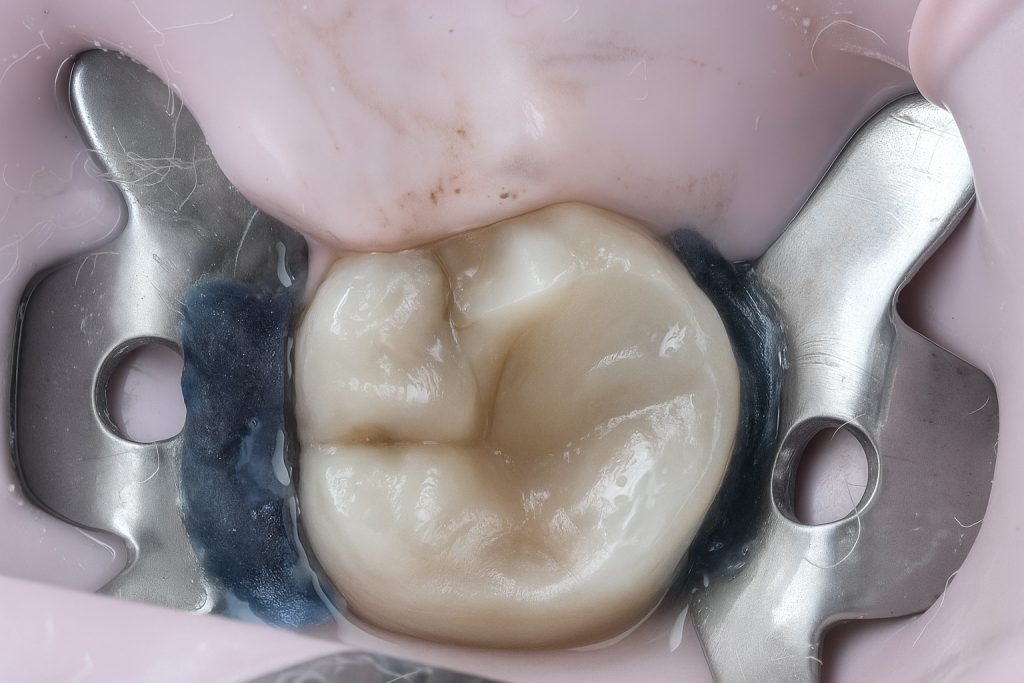

Full rubber-dam isolation was achieved using a pink dam for enhanced visibility (Fig 3). Conservative access under the dental microscope preserved pericervical dentin.

3️⃣ Rubber-dam isolation (pink dam)